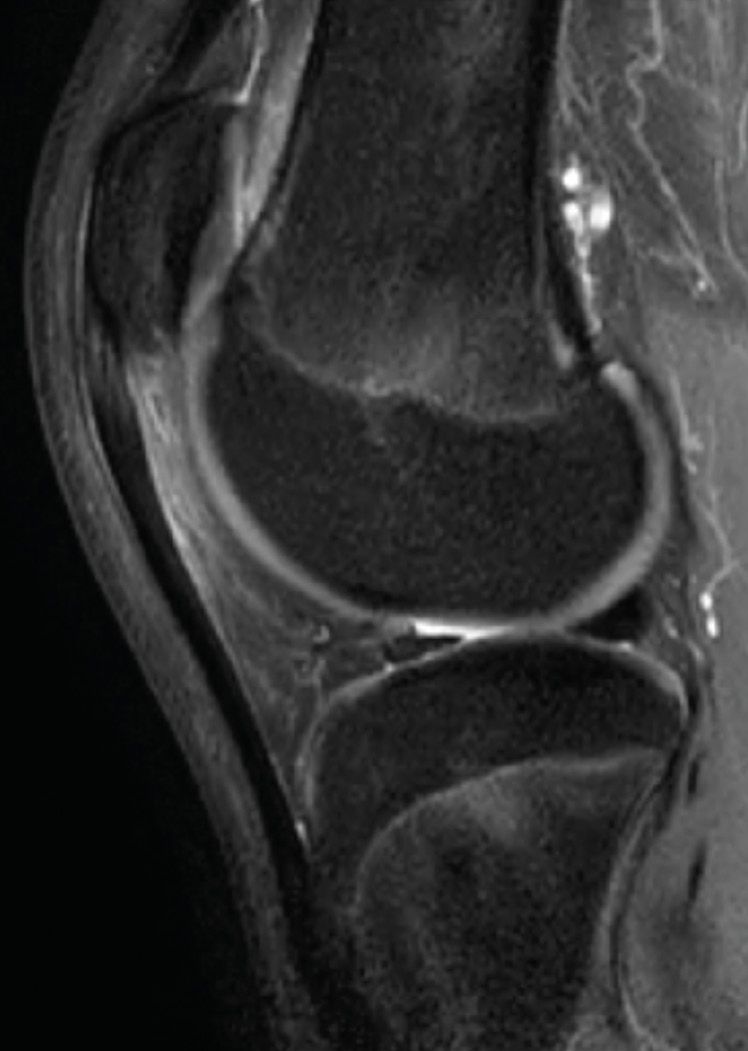

The only indication is patients with isolated patellofemoral pain syndrome and no objective instability, linked to patella alta (Fig. 1).

An MRI will provide additional information about any subchondral bony oedema, meniscus injury, patellar tendinopathy or Hoffa’s fat pad impingement (Fig. 2).